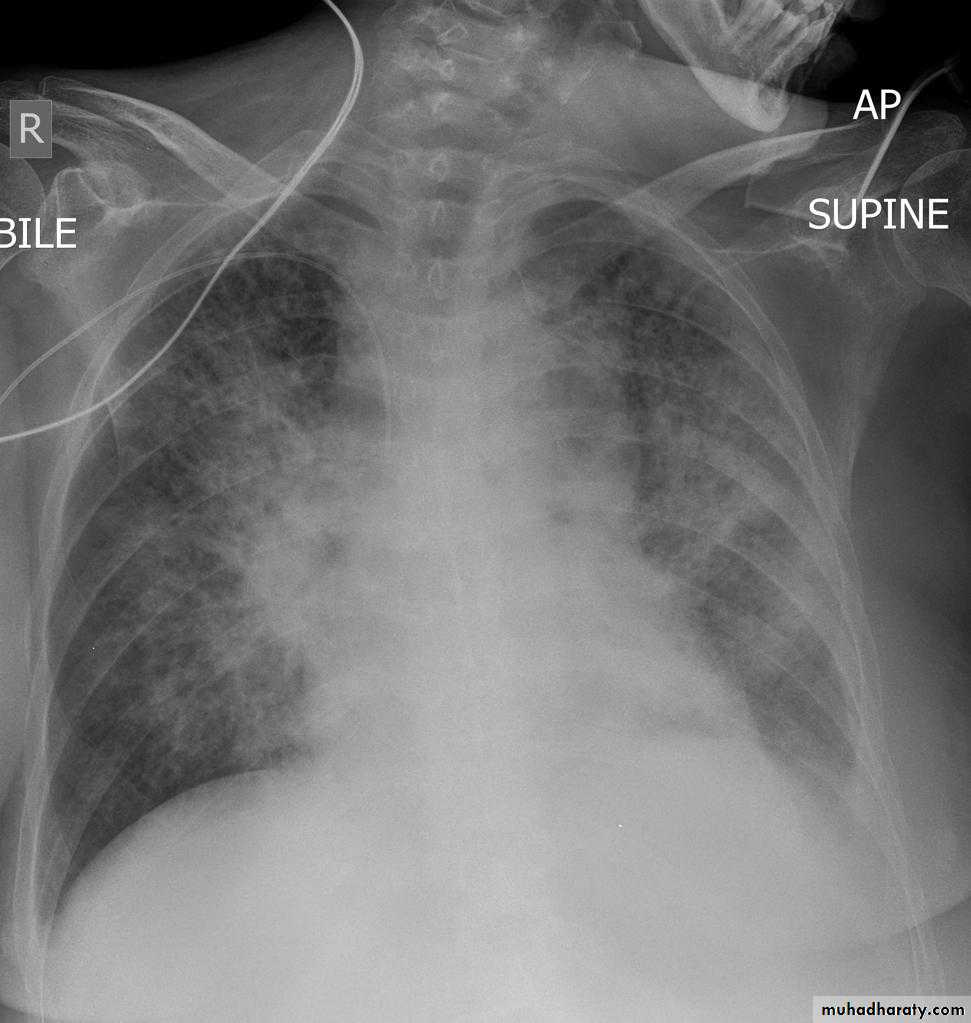

Radiographic features

Chest radiograph

With left sided congestive cardiac failure, the features are that of pulmonary edema which includes:

central pulmonary venous congestion ( prominent hilum )

cephalization of pulmonary veins ( upper lobe pulmonary venous diversion )

pulmonary interstitial edema

pulmonary alveolar edema

Cardiomegaly

Pleural effusion